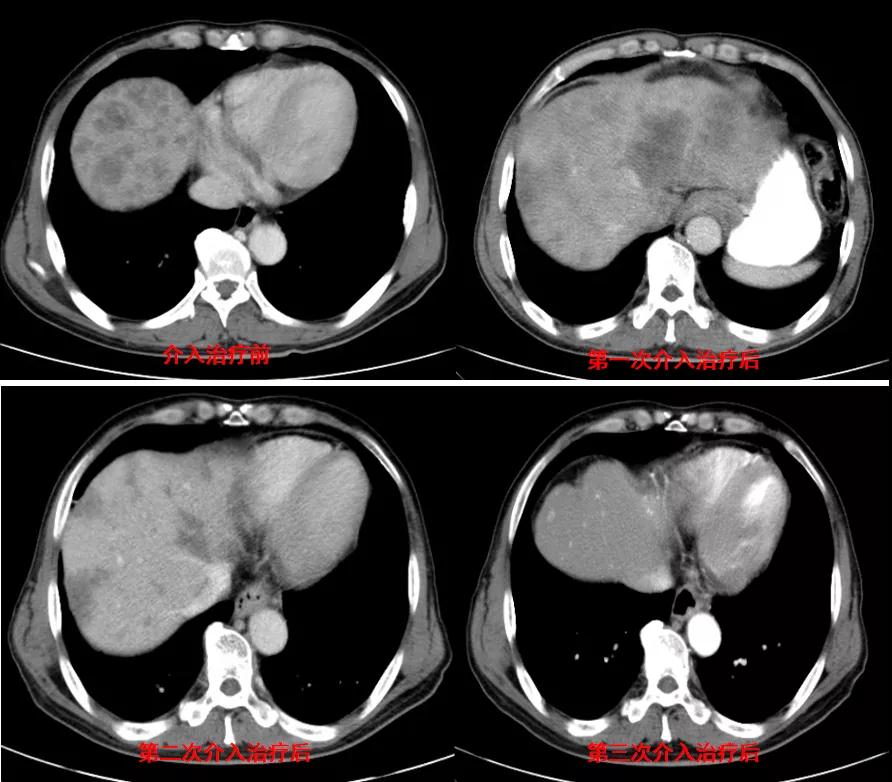

诊治经过:2020年12月16日患者行第二次经皮动脉化疗灌注栓塞术(铂类+氟尿嘧啶)治疗,并继续联合吡咯替尼治疗。结果见图3。

图3